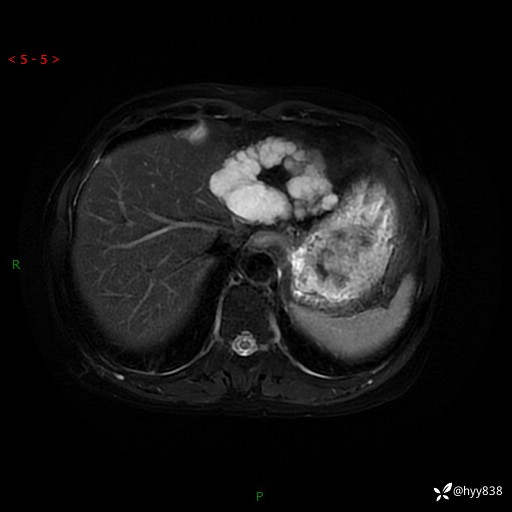

T2WIfs+DWI

增强(动脉期+静脉期+延迟期)